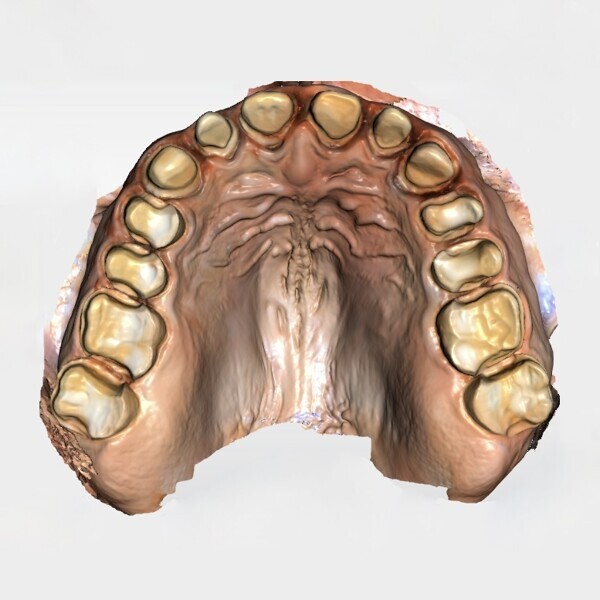

Fig. 1d: Almost complete loss of the occlusal relief in the upper jaw.

The clinical and radiographic examination revealed pronounced erosive defects on all teeth (Figs. 1a-f). To prevent nocturnal wear of the remaining tooth structure, an occlusal splint had been prepared by the patient’s general dentist in the past. Quick screening for temporomandibular disorder using the tool developed by the German Society of Craniomandibular Function and Disorders was carried out and revealed no functional abnormalities. The diagnosis was generalised, highly pronounced erosion due to exogenous acid (cola), abrasion and attrition with decreased OVD, multiple carious lesions, dentine hypersensitivity, gingivitis and compromised aesthetics.